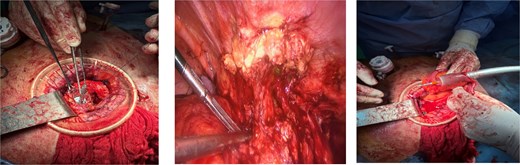

The patient underwent laparoscopic revision. Working trocars were placed, and pneumoperitoneum was established. Intraoperatively, an inflammatory mass with adhesions to the anterior abdominal wall was identified at the previous laparotomy site. Careful adhesiolysis was performed, preserving viable tissue, and the cecum was freed from its attachment to the prior McBurney incision. The terminal ileum and ascending colon were mobilized. A relaparotomy was then performed through the previous incision, and a wound protector was placed to exteriorize the inflammatory block. The terminal ileum was transected 15 cm proximal to the ileocecal valve, and the ceco-ascending colon was divided just above the pathological segment. An extracorporeal side-to-end ileocolic anastomosis was constructed using a circular stapler (Fig. 2). Peritoneal lavage was performed, hemostasis was verified, and a drain was placed through one of the ports. The abdominal wall at the relaparotomy site was repaired, and four primary-delayed skin sutures were placed with a Betadine-soaked gauze. The procedure was completed without intraoperative complications.

On the sixth postoperative day, due to the development of fever, the primary-delayed sutures were removed to allow the wound to heal by secondary intention (per secundam). On the tenth postoperative day, negative pressure wound therapy (NPWT) was applied. The patient was discharged in good general condition with the vacuum system (NPWT) in place (Fig. 3).